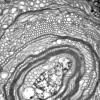

PERIPHERAL NEUROPATHY